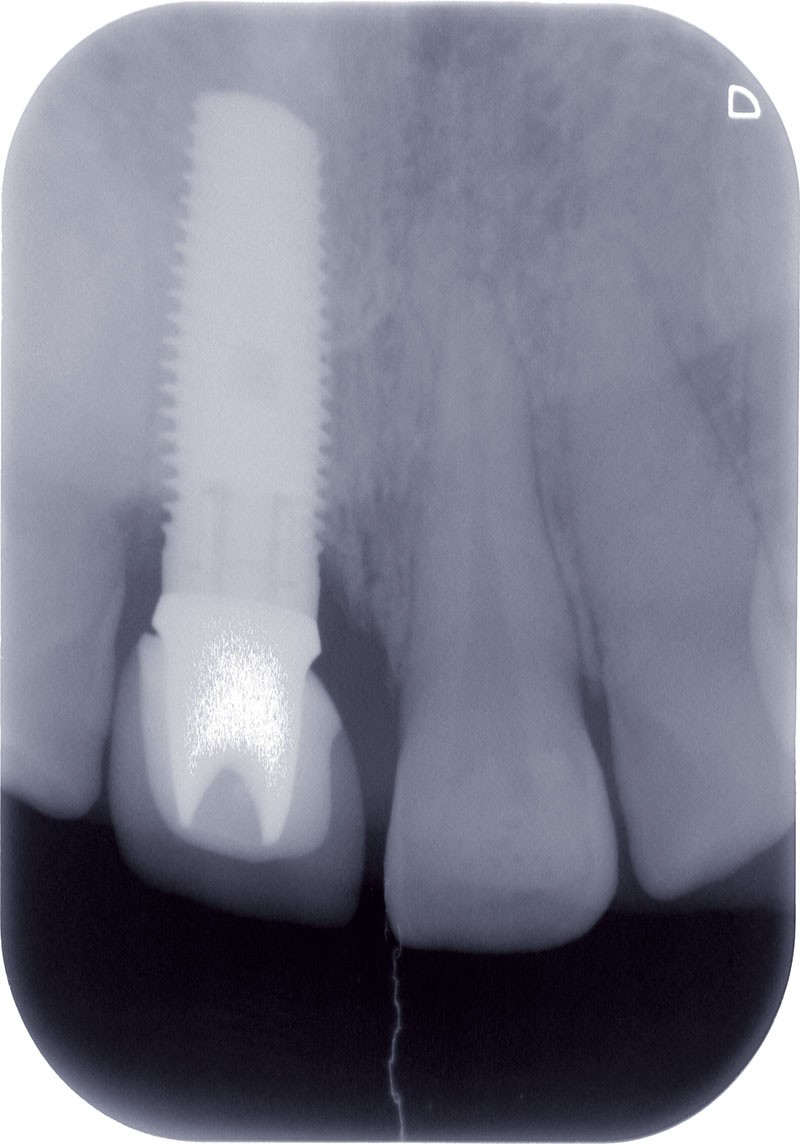

La radiographie ne révèle aucun problème d’ostéointégration implantaire (fig. 1b).